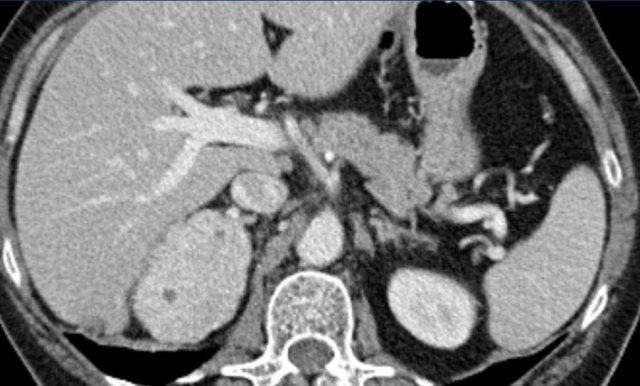

Các hình ảnh cho thấy u tình cờ tuyến thượng thận hai bên được phát hiện ở bệnh nhân 64 tuổi được chụp CT để phân tích phình động mạch chủ bụng.

Hình chụp pha động mạch cho thấy các tổn thương hai bên với tỷ trọng 50 HU.

Trên CT không tiêm thuốc thực hiện vài ngày sau, tỷ trọng ở cả hai tuyến thượng thận đều dưới 10 HU, xác nhận đây là các u tuyến giàu lipid.